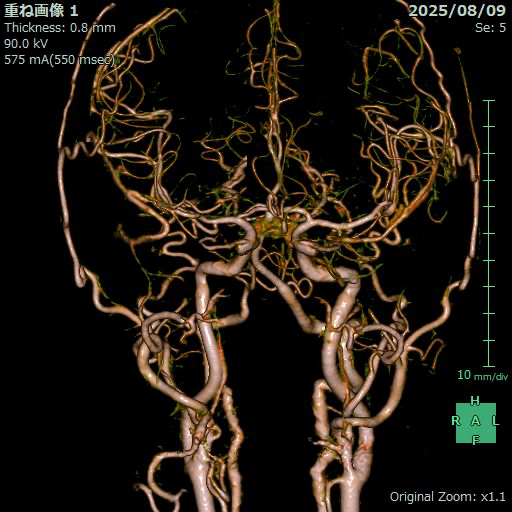

脳血管画像

脳血管3D画像

頸部血管画像

アンギオ装置

肘や太ももの付け根の動脈からカテーテルと呼ばれる細い管を挿入し、造影剤という薬剤を流し込みながら X 線撮影を行うことで、血管の状態や、流れを観察する検査です。

これにより血管にできたコブ(動脈瘤)、血管の狭窄、血管奇形、腫瘍などをより正確に把握し、今後の治療方針の検討を行います。

当院のアンギオ装置Artis zeeはフラットパネル血管造影システムにより、従来装置と比較して約50%の被曝量削減を実現しています。また3D撮影することにより的確な画像を提供することができます。

当院では必要に応じて脳血管内治療(IVR)も行います。

脳動脈瘤のコイル塞栓術や、脳血管の狭窄に対するステント留置術など、IVR(インターベンショナル・ラジオロジー:)と呼ばれる血管内治療に対応しています。